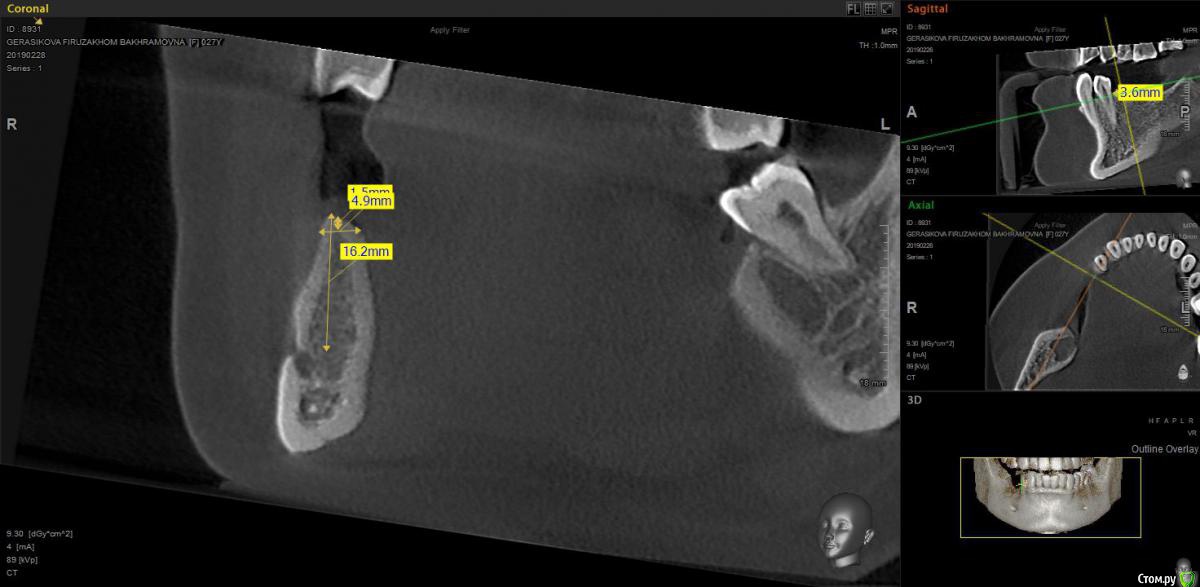

moises Опубликовано 28 февраля, 2019 Поделиться Опубликовано 28 февраля, 2019 Добрый вечер!Планируется имплантация 45 и 47.В области 45 хочу установить 3,5x10 субкрестально на 1мм.Но,как я понимаю,с таким диаметром имплантата костной пластики не избежать.Коллеги,посоветуйте,как лучше тут ее спланировать(материалы,методика)?Это будет 1й опыт костной пластики,поэтому ценны любые комментарии Ссылка на комментарий

red_butler Опубликовано 2 марта, 2019 Поделиться Опубликовано 2 марта, 2019 Срезы выставленны не корректно Ссылка на комментарий

moises Опубликовано 3 марта, 2019 Автор Поделиться Опубликовано 3 марта, 2019 Срезы выставленны не корректнопочему? что неправильно? Ссылка на комментарий

red_butler Опубликовано 3 марта, 2019 Поделиться Опубликовано 3 марта, 2019 почему? что неправильно?близко к зубу Ссылка на комментарий